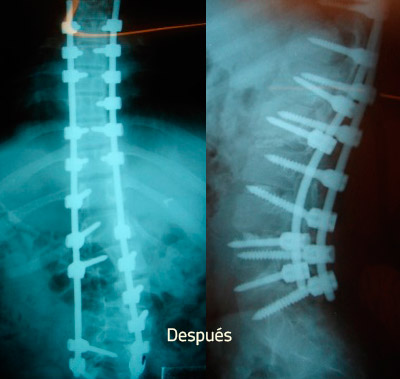

CIRUGÍA DE ESCOLIOSIS

Realizar una cirugía de escoliosis lleva varias horas por su complejidad, la hospitalización es prolongada y algunas actividades estarán restringidas por varios meses; pero tiene un alto porcentaje de éxito en detener y corregir la deformidad de la columna vertebral.

Casos

E.B. 16 años, lo diagnosticamos con Escoliosis Ideopática Juvenil y su operación duró 7 horas. Él fue uno de nuestros casos complejos de escoliosis tratados con éxito.